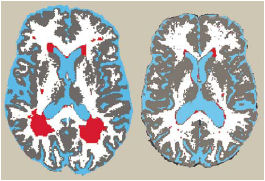

In a new study, greater consumption of either nutrient correlated with more and bigger brain lesions in elderly volunteers.

“I’m talking about damage that you can see in white matter or gray matter of the brain,” explains study leader Martha E. Payne of Duke University in Durham, N.C. “We think these lesions are due to a lack of oxygen to [affected] areas,” she reported May 1 at the Experimental Biology meeting in Washington, D.C.

Everyone had lesions, which typically develop with age. However, after accounting for factors associated with a greater risk of lesions, such as high blood pressure, the researchers found that the degree of damage generally tracked the elderly people’s intakes of calcium and vitamin D.